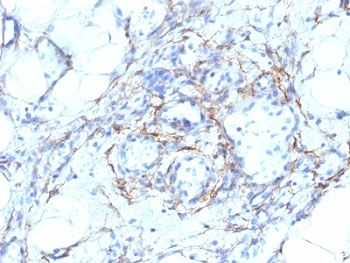

IHC: Formalin-fixed, paraffin-embedded human angiosarcoma stained with SMMHC antibody (MYH11/923).